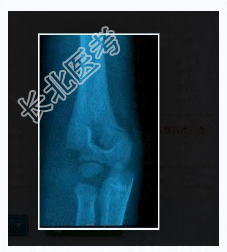

多项选择题3.提示:左上肢X线片如图所示。      诊断考虑为

A、左肱骨干骨折

B、左肱骨外科颈骨折

C、左肱骨外髁骨折

D、左桡骨小头骨折

E、左尺骨骨折

F、左肱骨髁上骨折